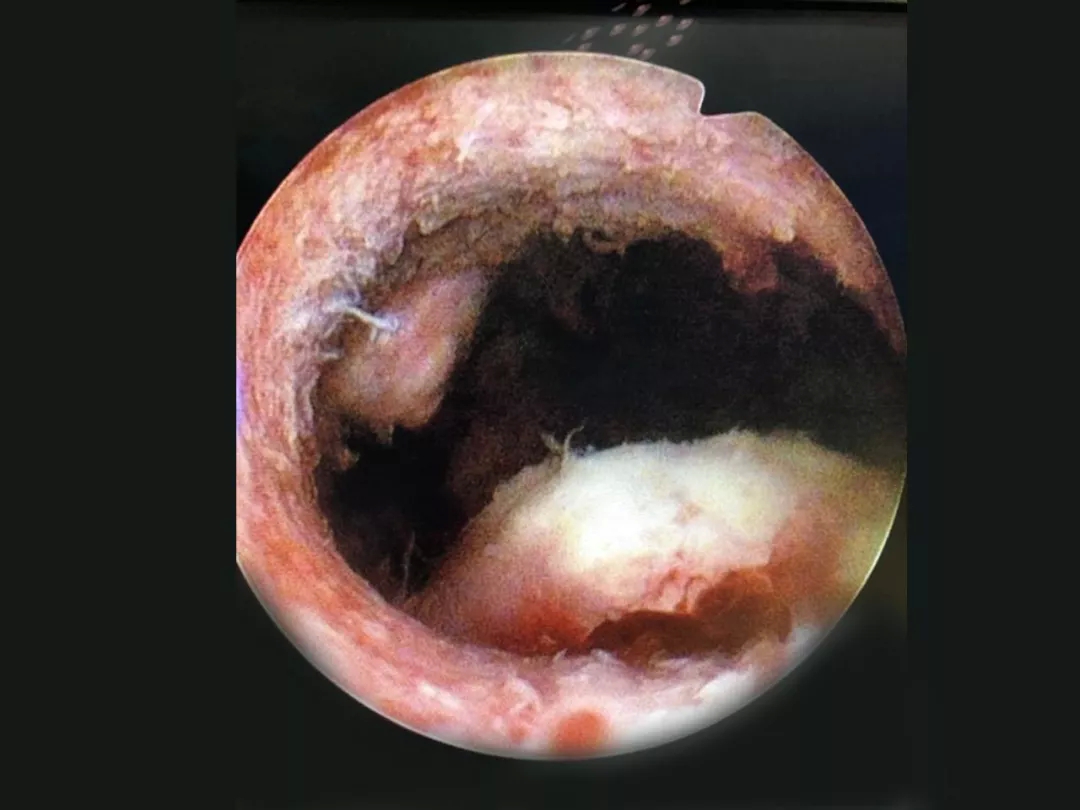

宫腔镜下的子宫内膜息肉

子宫内膜癌

孙大娘经宫腔镜下取标本,病理证实是子宫内膜癌,后续作了根治手术。因为发现的及时,术后证实为早期,预后非常好。